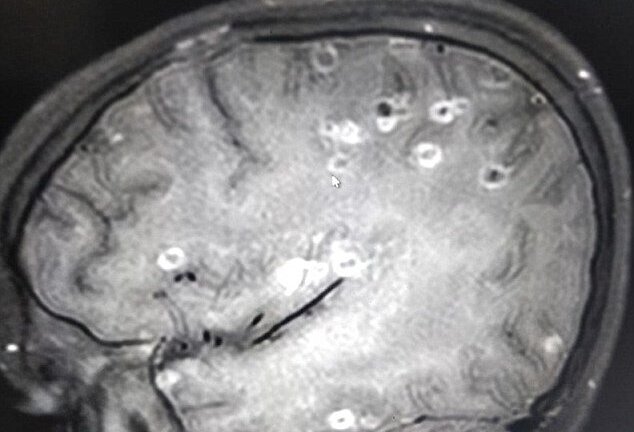

Trứng sán từ dạ dày 'chạy' lên não theo đường máu, cô bé có 100 trứng sán dây trong đầu

Một bé gái 8 tuổi bị đau đầu tê liệt, co giật và lên cơn động kinh, sau khi nhập viện cả người nhà và bác sĩ đều sửng sốt khi phát hiện 100 trứng sán dây trong não cô bé.